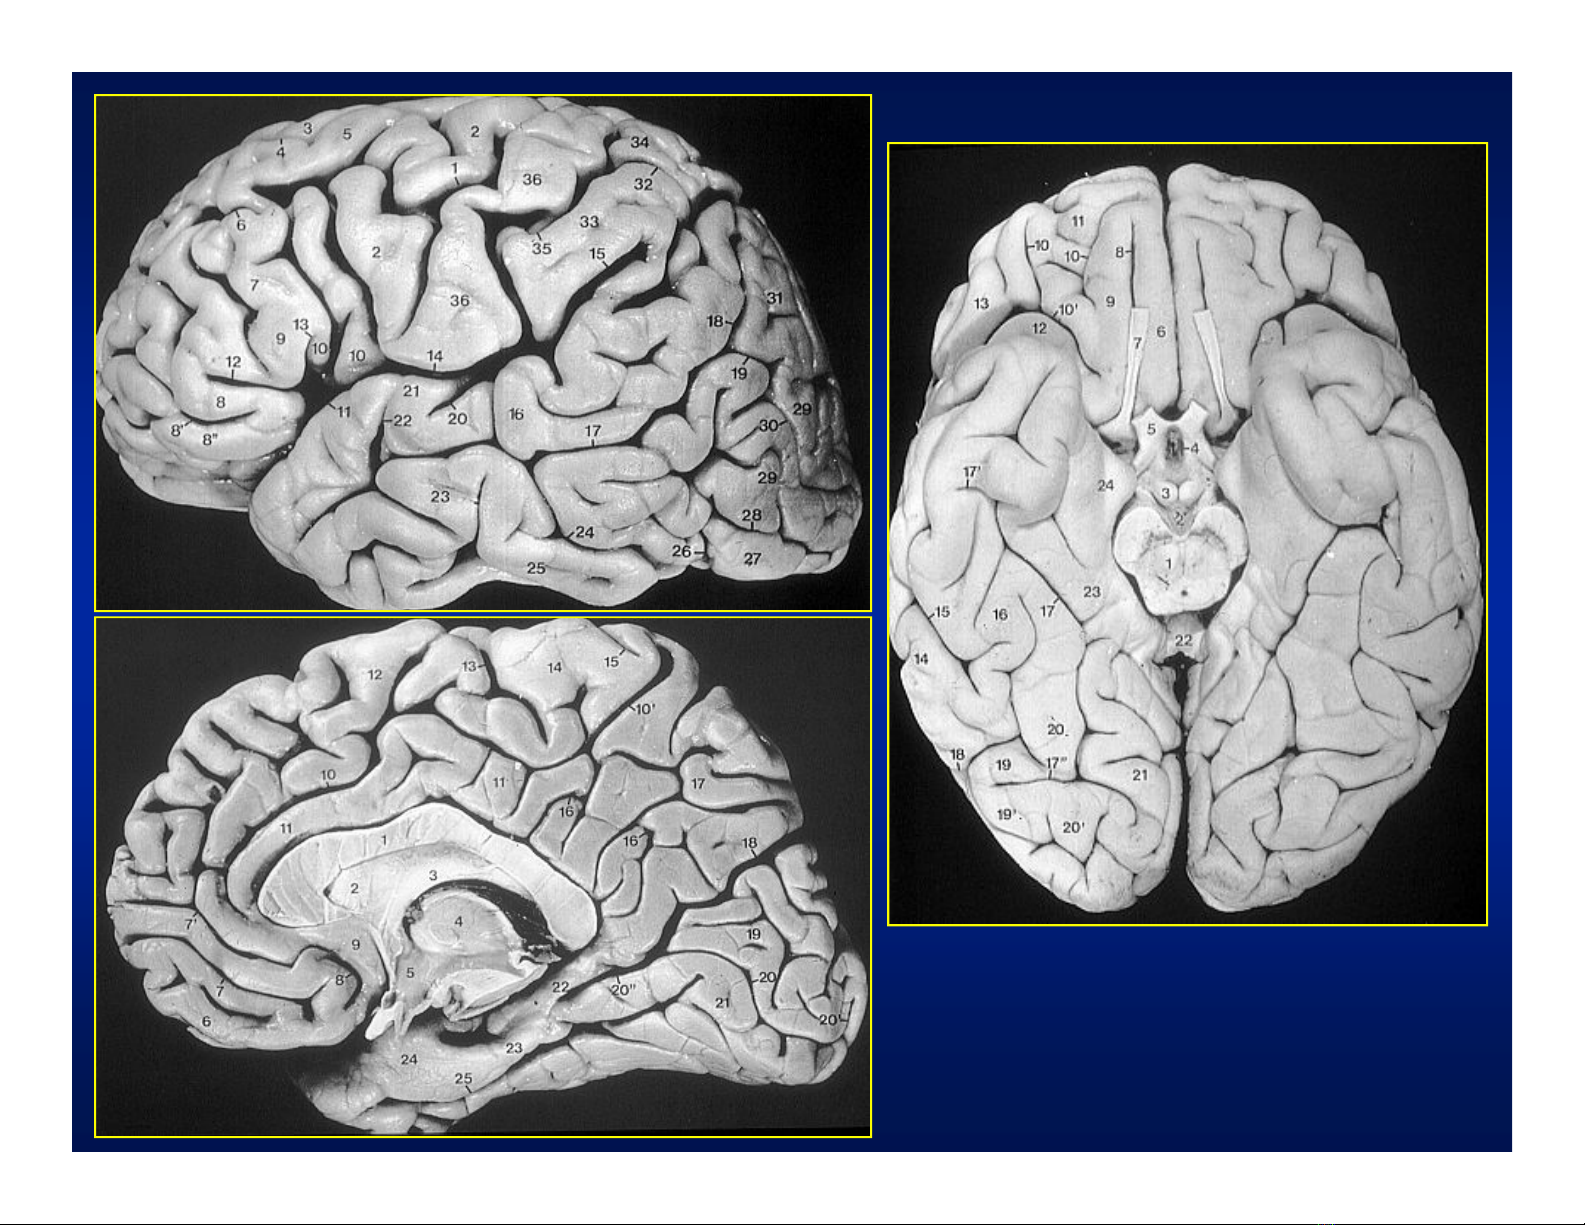

Gi¶i phÉu nhu m« n·oGi¶i phÉu nhu m« n·o

1.Thuú tr¸n

2.Thuú ®Ønh

3.Thuú chÈm

4.Thuú th¸i d- ¬ng

5.R·nh Rolando

C¸c thuú n·oC¸c thuú n·o

Gi¶i phÉu nhu m« no